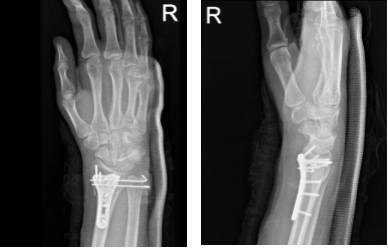

At 32 weeks post operative, the patient tolerated activities and returned to his normal routine. Patient gets well from his surgery with consistent visits to our office.